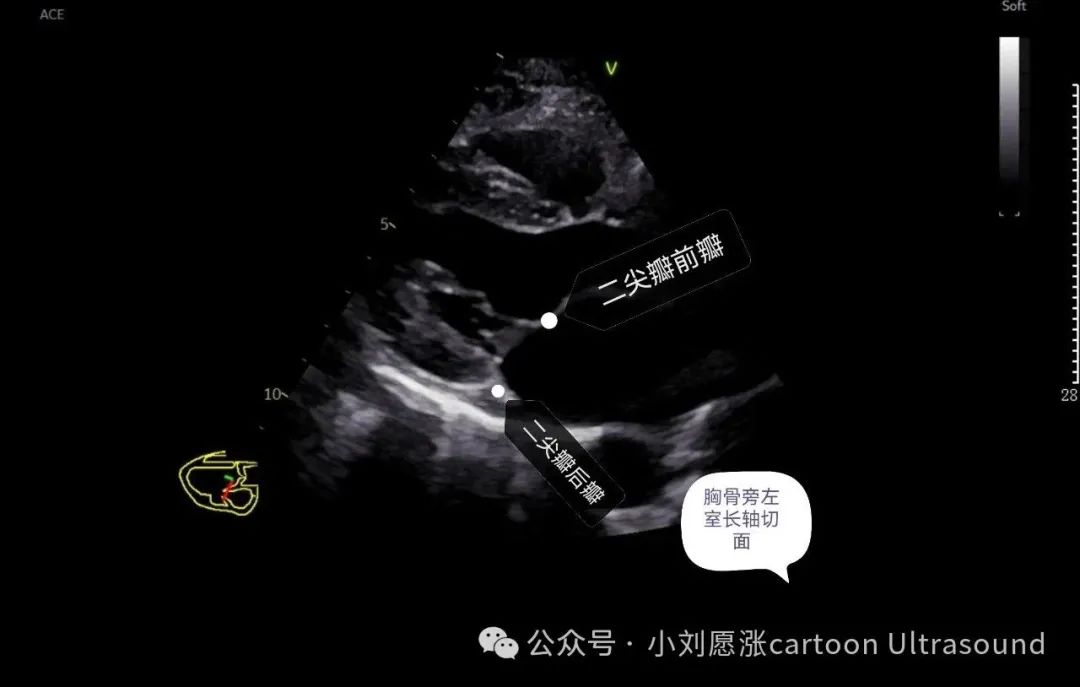

二尖瓣:2个瓣叶,分前瓣、后瓣。